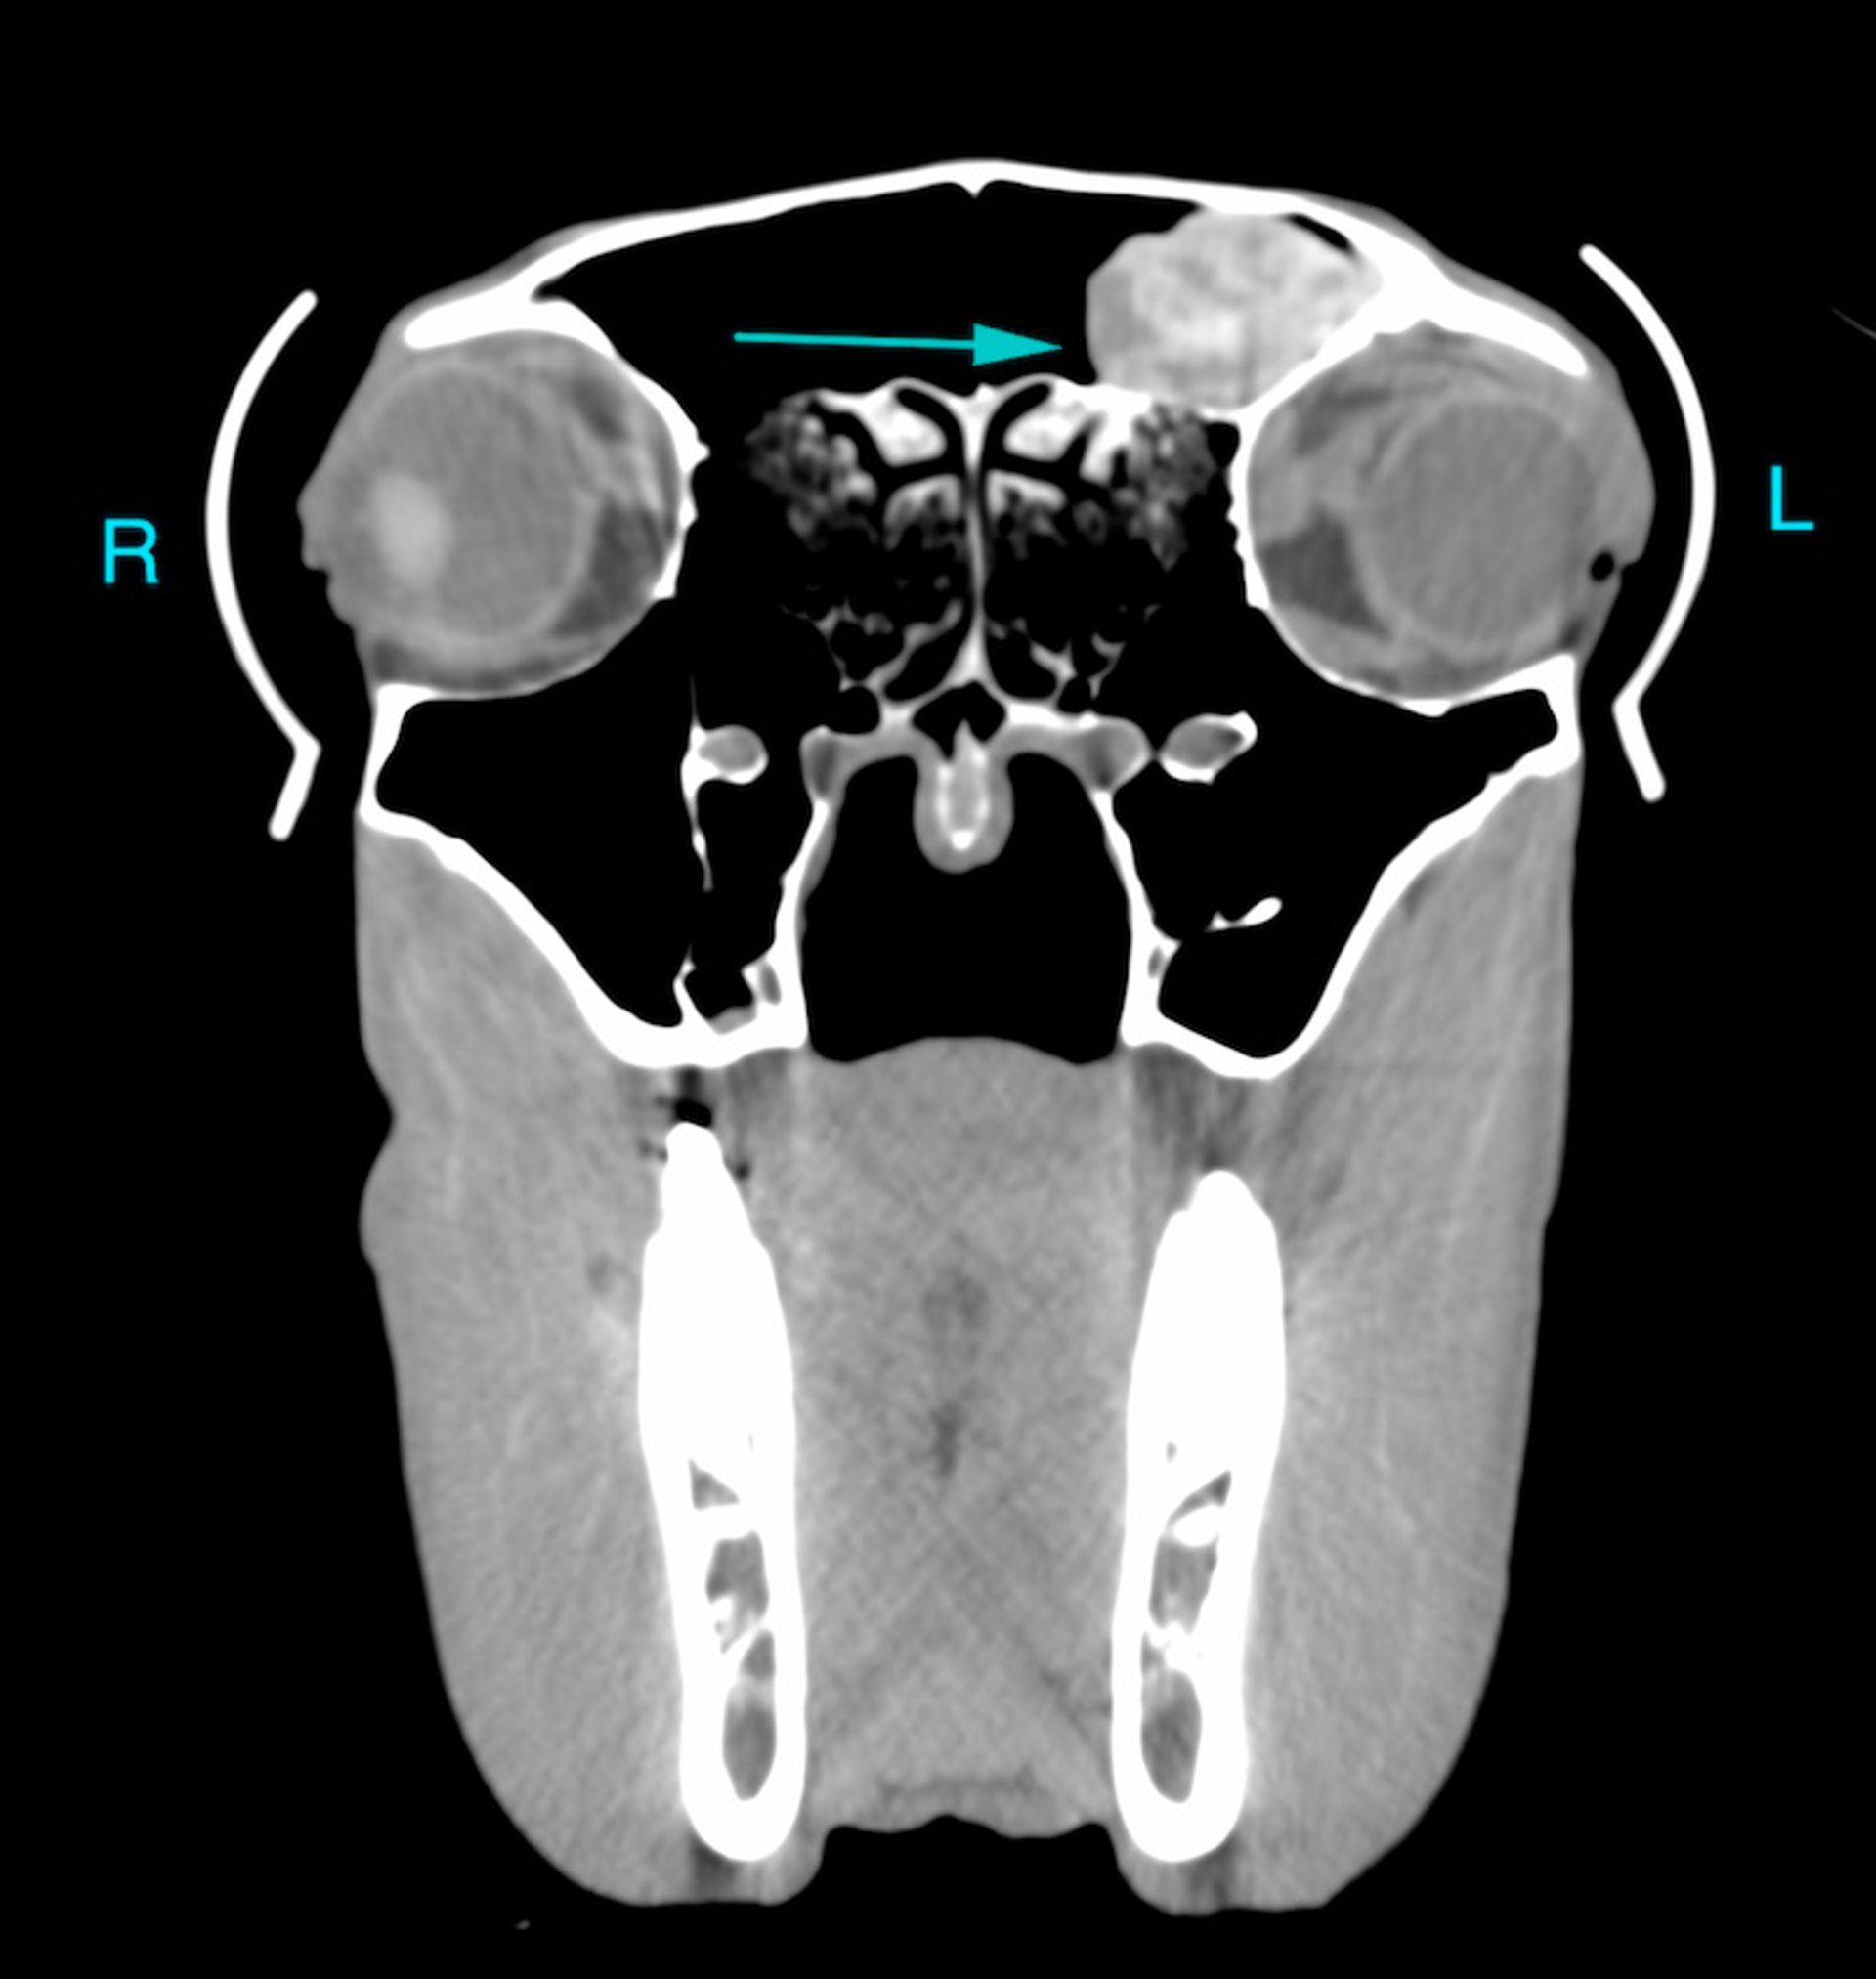

Imagen de TC transversal del cráneo de un caballo visualizada en una ventana de tejidos blandos. El lado izquierdo del paciente está a la derecha de la imagen. Se encuentra dentro del seno frontal izquierdo una masa bien definida que se atenúa mediante tejido blando con múltiples regiones de marcada hiperatenuación (flecha). Finalmente se determinó que se trataba de un hematoma etmoidal. Esto puede haber sido identificable pero caracterizado de forma incompleta en las radiografías de cráneo; sin embargo, la TC permite una evaluación completa y puede guiar potencialmente el tratamiento posterior, por ejemplo con cirugía.

Cortesía del Dr. Timothy Manzi.